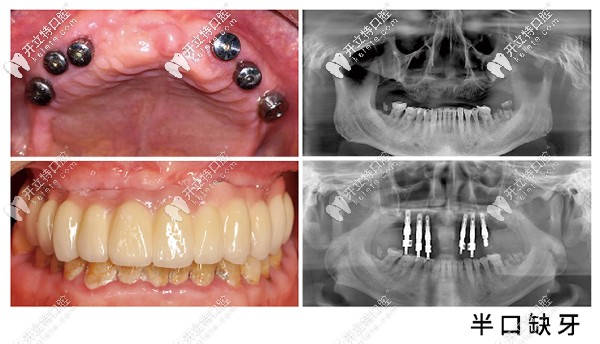

昆明美奧口腔半口種植牙案例

一般在昆明做半口種植牙價格在8萬以上,所以昆明美奧口腔收費不算貴。咱們要知道種牙不僅要看價格,醫(yī)生技術也是考驗后期使用長短的。